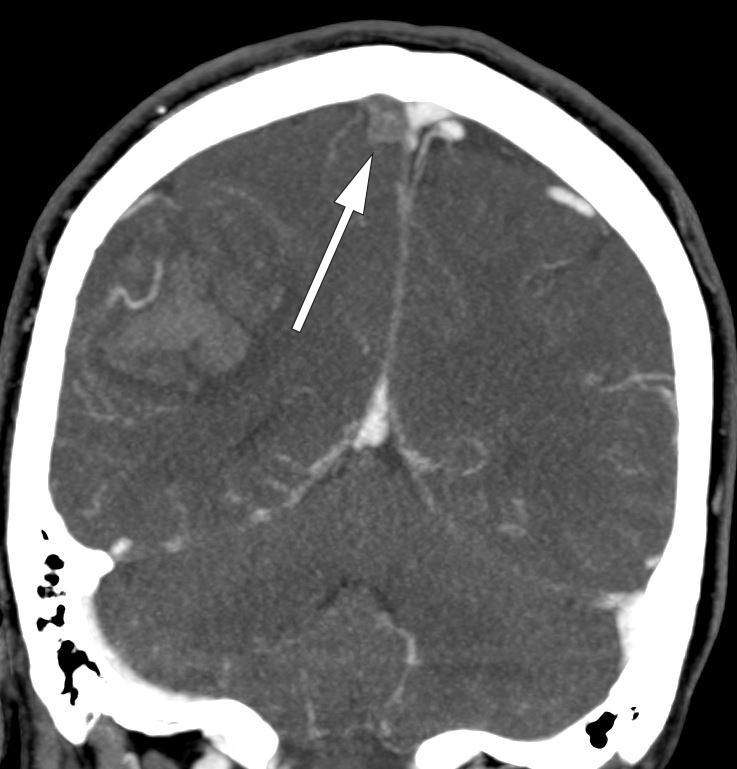

Det cerebrale venesystemet er bygd opp av et overfladisk og et dypere venesystem (fig 1) (3, 8).

En obstruksjon som følge av en venøs trombe i durale/kortikale vener eller venesinus (fig 2) vil gi økt venøst trykk og redusert kapillær perfusjon. Dette vil initialt bli kompensert via det omfattende cerebrale kollaterale nettverket, men når kapasiteten også i dette nettverket overskrides, vil det utvikle seg venøs stase, økt intramuralt trykk, skade på venene og blod-hjerne-barrieren, og dermed utvikling av vasogent ødem og hemoragiske infarkter. I tillegg vil den reduserte cerebrale perfusjonen føre til cytotoksisk ødem og ytterligere økning av intrakranialt trykk. Obstruksjon av cerebrale sinuser kan også resultere i redusert absorbsjon av cerebrospinalvæske og dermed ytterligere økt intrakranialt trykk.

Ved sterk klinisk mistanke om cerebral venetrombose, eller dersom man på CT caput finner lobære parenkymblødninger eller infarktforandringer som ikke følger de vanlige arterielle kargebetene, må cerebral venetrombose mistenkes og ytterligere bildeundersøkelser gjennomføres (1–3). CT caput uten kontrast har dårlig sensitivitet (40–70 %), og tillegg av intravenøs kontrast kan vise en hyperdens fyllingsdefekt i venesinusene (inkludert såkalt tomt deltategn i sinus sagittalis superior), men fortsatt ser man verken direkte eller indirekte tegn på cerebral venetrombose ved CT-undersøkelse hos mer enn 30 % (3, 12).

Både CT- og MR-venografi kan bekrefte diagnosen cerebral venetrombose, men MR-venografi er trolig mer sensitiv i den akutte fasen (3, 13, 14). Hjerneparenkymet, venøse infarkter og blødninger blir bedre fremstilt ved MR-venografi slik at dette er den foretrukne modaliteten (1). Venøse infarkter forekommer hos omtrent 60 % av pasientene og avviker fra de arterielle infarktene ved at deres utstrekning går utover de vanlige kargebetene (3).

Vi takker nevroradiolog Svetozar Zarnovicky ved Radiologisk avdeling, Akershus universitetssykehus for hjelp med bildet som illustrerer denne artikkelen.